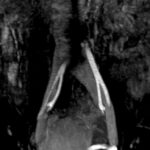

Fig. 8 y Fig. 9. AngioRM demostrando la dilatación de la VICI luego del pasaje entre AICD y la columna.

Se corrobora el diagnóstico presuntivo con flebografía y angioresonancia, observándose compresión de la VICI entre la columna y AICD y su dilatación distal (Fig. 8 y Fig. 9).